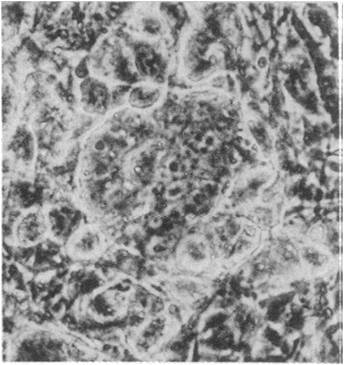

馬丁·約翰·伊文思爵士分離培養(yǎng)的小鼠胚胎干細(xì)胞